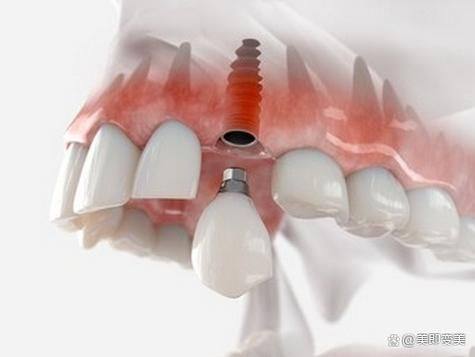

3. 种植牙技术:陈俊龙医生在种植牙方面有着独特的技术优势。他发明的陈氏五合一植牙法结合了多项植牙专项,为患者提供了更效率高、更安心的种植牙解决方案。这种植牙法能够缩短种植时间,提高种植成功几率,让患者更快地修复牙齿功能。同时,他还发明了HSC陈氏水压法鼻窦增高术和VTT陈氏牙龈拉皮法,为种植牙手术提供了更好的基础条件。

1. 创新的技术发明:陈俊龙医生发明了HSC陈氏水压法鼻窦增高术、VTT陈氏牙龈拉皮法和陈氏五合一植牙法等多项技术。这些技术的发明为相关疾病的治疗提供了新的思路和方法。例如,陈氏五合一植牙法结合了多项专项技术,能够提高种植牙的成功几率和效率,减少患者的痛苦和治疗时间。

3. 个性化治疗方案:陈俊龙医生会根据患者的具体情况制定个性化的治疗方案。在治疗过程中,他会充分考虑患者的年龄、身体状况、病情重度程度等因素,选择更适合患者的治疗方法。例如,在种植牙手术中,他会根据患者的口腔情况和需求,选择合适的种植体和种植方案,确保手术的成效和安心性。

3. 患者王先生牙齿缺失多年,一直想进行种植牙手术。他了解到陈俊龙医生在种植牙方面有独特的技术,于是找到了陈医生。陈医生根据王先生的口腔情况,采用陈氏五合一植牙法为他进行了种植牙手术。手术非常顺利,术后王先生的牙齿修复了正常的功能。王先生评价说:“陈医生的种植牙技术真的太棒了,手术时间短,成效还好。现在我又可以正常吃东西了,生活质量提高了特别多。陈医生是一位非常值得信赖的医生。”